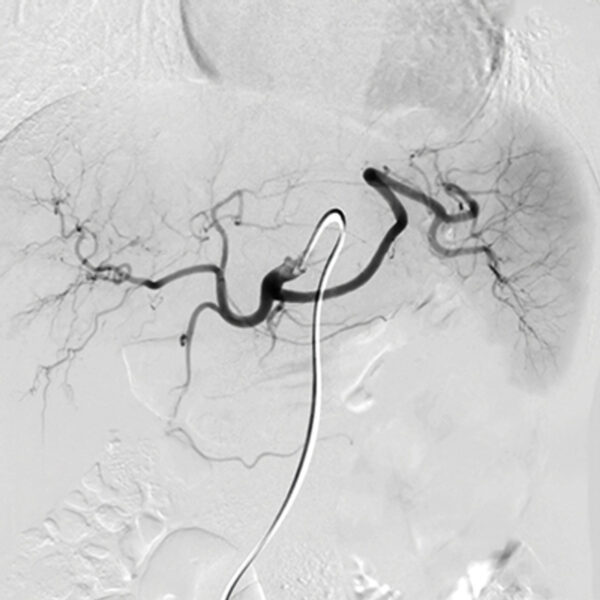

- Catheter Directed Therapies for Acute Pulmonary Embolism – Bedros Taslakian, MD

- Vascular Malformations – Frederic J. Bertino, MD

- Mesenteric Ischemia – Amir Noor, MD